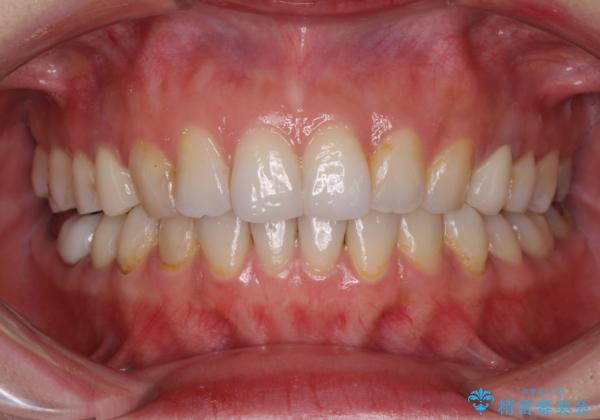

- 失活により変色した歯と不揃いな口元を気にして来院された患者様です。

口元をインビザラインにより歯列を整え、その後に失活している奥歯をオールセラミッククラウンにて補綴治療することとしました。

長時間のマウスピース装着と、患者様自身でのゴムかけに協力いただき、自然な口元に仕上げることができました。

気になっていた変色した歯もオールセラミッククラウンで本物の歯のようになり、患者様には大変満足していただきました。